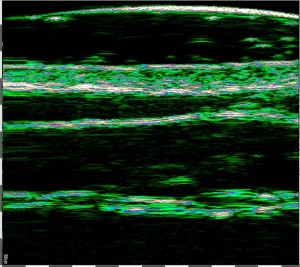

-Υπέρηχος Υψηλής Συχνότητας (HFUS) και Ιστολογία

Εφαρμογές δερματολογίας

-Κύριες εφαρμογές